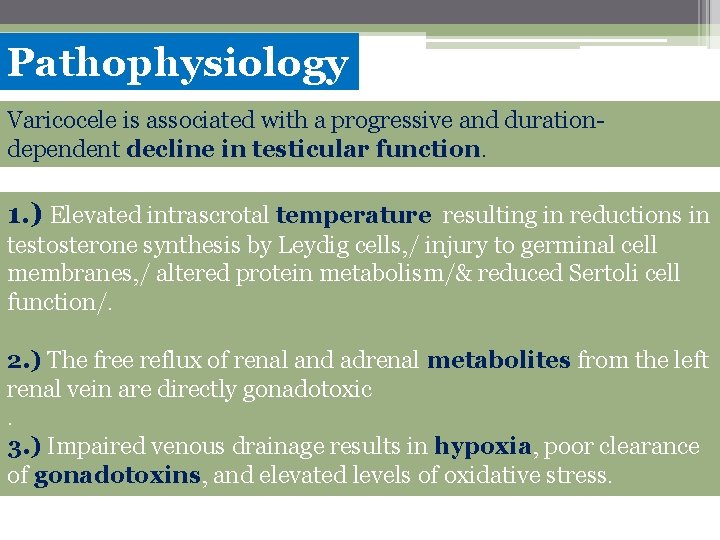

Pathophysiology Varicocele is associated with a progressive and durationdependent decline in testicular function. 1. ) Elevated intrascrotal temperature resulting in reductions in testosterone synthesis by Leydig cells, / injury to germinal cell membranes, / altered protein metabolism/& reduced Sertoli cell function/. 2. ) The free reflux of renal and adrenal metabolites from the left renal vein are directly gonadotoxic. 3. ) Impaired venous drainage results in hypoxia, poor clearance of gonadotoxins, and elevated levels of oxidative stress.